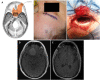

Background: Keyhole craniotomies are increasingly being used for lesions of the skull base. Here we review our recent experience with these approaches for resection of intracranial meningiomas.

Methods: Clinical and operative data were gathered on all patients treated with keyhole approaches by the senior author from January 2012 to June 2013. Thirty-one meningiomas were resected in 27 patients, including 9 supratentorial, 5 anterior fossa, 7 middle fossa, 6 posterior fossa, and 4 complex skull base tumors. Twenty-nine tumors were WHO Grade I, and 2 were Grade II.

Results: The mean operative time was 8 hours, 22 minutes (range, 2:55-16:14) for skull-base tumors, and 4 hours, 27 minutes (range, 1:45-7:13) for supratentorial tumors. Simpson Resection grades were as follows: Grade I = 8, II = 8, III = 1, IV = 15, V = 0. The median postoperative hospital stay was 4 days (range, 1-20 days). In the 9 patients presenting with some degree of visual loss, 7 saw improvement or complete resolution. In the 6 patients presenting with cranial nerve palsies, 4 experienced improvement or resolution of the deficit postoperatively. Four patients experienced new neurologic deficits, all of which were improved or resolved at the time of the last follow-up. Technical aspects and surgical nuances of these approaches for management of intracranial meningiomas are discussed.

Conclusions: With careful preoperative evaluation, keyhole approaches can be utilized singly or in combination to manage meningiomas in a wide variety of locations with satisfactory results.